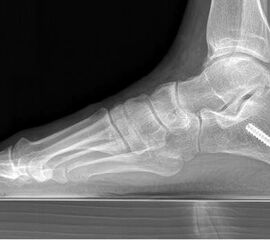

Abbildung Nr. 1: Röntgen Fuß: dp und seitlich stehend.

715.<br> Für die medialisierende Calcaneusosteotomie wird ein bogenförmiger Hautschnitt in Höhe des hinteren Fersenbeines gesetzt, die Subcutis bis zum Fersenbein durchtrennt und dieser bogenförmige Lappen nach ventral präpariert. Dadurch kommt es zu einem Schutz des Nervus suralis, welcher gemeinsam mit den Peronealsehnen nach vorne gehalten wird.<br> Es wird nun das Fersenbein mit einem Wundspreizer eingestellt und cranial sowie caudal mit 2 Hohmannhaken umfahren.<br> Dann wird das Fersenbein mit der oszillierenden Säge osteotomiert, mit dem Meißel und dem Wundspreizer distrahiert.<br> Danach wird das Fersenbein ca. 1 cm nach medial verschoben, unter Vermeidung der Cranialisierung des hinteren Calcaneus . Dann wird von dorsal über eine Hautstichincision der Bohrdraht für die 4,5mm (- 6,5 mm) kanülierte Schraube eingebracht und über die Osteotomie in den vorderen Calcaneusanteil vorgeschoben.<br> Kontrolle im Bildwandler in 2 Ebenen. Wenn die Bohrdrahtlage gut ist Überbohren für die kanülierten Schrauben und Eindrehen der Schraube. (Alternativ kann an Stelle der Schraubentechnik auch eine Fixation mit Stufenplatten oder Ähnlichem verwendet werden).<br> Wundverschluss am lateralen Zugang und über der Stichincision.</p>"> 715.<br> Für die medialisierende Calcaneusosteotomie wird ein bogenförmiger Hautschnitt in Höhe des hinteren Fersenbeines gesetzt, die Subcutis bis zum Fersenbein durchtrennt und dieser bogenförmige Lappen nach ventral präpariert. Dadurch kommt es zu einem Schutz des Nervus suralis, welcher gemeinsam mit den Peronealsehnen nach vorne gehalten wird.<br> Es wird nun das Fersenbein mit einem Wundspreizer eingestellt und cranial sowie caudal mit 2 Hohmannhaken umfahren.<br> Dann wird das Fersenbein mit der oszillierenden Säge osteotomiert, mit dem Meißel und dem Wundspreizer distrahiert.<br> Danach wird das Fersenbein ca. 1 cm nach medial verschoben, unter Vermeidung der Cranialisierung des hinteren Calcaneus . Dann wird von dorsal über eine Hautstichincision der Bohrdraht für die 4,5mm (- 6,5 mm) kanülierte Schraube eingebracht und über die Osteotomie in den vorderen Calcaneusanteil vorgeschoben.<br> Kontrolle im Bildwandler in 2 Ebenen. Wenn die Bohrdrahtlage gut ist Überbohren für die kanülierten Schrauben und Eindrehen der Schraube. (Alternativ kann an Stelle der Schraubentechnik auch eine Fixation mit Stufenplatten oder Ähnlichem verwendet werden).<br> Wundverschluss am lateralen Zugang und über der Stichincision.</p>" srcset="/assets/images/a/3-raswd6qgkh6s353.jpg 1x, /assets/images/g/3-exngvjjv83x827d.jpg 1.5x, /assets/images/w/3-836r57qt8j3eh0w.jpg 2x" width="270" height="240" loading="lazy">